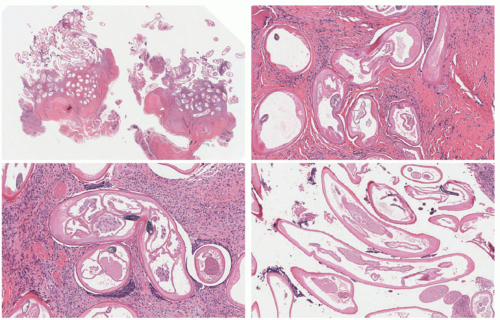

Viable cysticerci may be seen in tissue, compressing adjacent structures, but causing virtually no inflammatory response. When the whole larva is present, it is seen as a cystic structure surrounded by a vesicular wall. The lumen is folded and ribbon-like and contains the invaginated scolex. Occasionally, sucking discs and hooklets can be seen. Hooklets have a distinctive histologic appearance, as they appear as brown, refractile, sickle-shaped structures. However, when cysticerci degenerate, they elicit an inflammatory reaction with infiltration by neutrophils, histiocytes, and eosinophils. (Figures 21-5 and 21-6) A granulomatous reaction eventually develops, characterized by the presence of histiocytes, epithelioid cells, and foreign body giant cells. Ultimately, this leads to fibrosis and calcification.17,23,25,26

Onchocercal nodules usually contain several adult worms in the dermis surrounded by an inflammatory reaction that varies from suppurative to granulomatous, with fibrosis36 (Figures 21-8 and 21-9). The organizing inflammatory process can also be associated with calcification and ossification. A layer of fibrinoid material may be seen covering the worms. The overlying epidermis shows hyperpigmentation with acanthosis and melanin pigment incontinence.